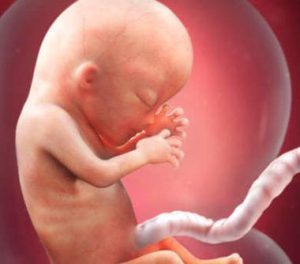

13週目に入ると、お腹の中の赤ちゃんも新たなステージを迎えます。身長は6.5から10㎝になり、体重は13~20グラムになります。

顔は個性を持った形に変化していき、その他体全体の形も出来上がってきます。このように、13週目には、とても素晴らしい変化が始まるのです!

赤ちゃんの目や耳の最終的な形が出来上がり、驚くべきことに、指紋はすでに存在しています。

臓器の構築に欠かせない脳は、赤ちゃんの体の中でも最も早く形成される部分の1つです。

この時点では、頭の大きさは胎児の体の半分を締めています。

その後、体の部分が成長し始め、適切にバランスの取れた体になっていきます。